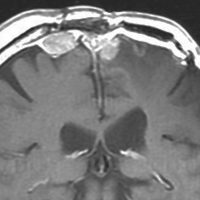

最も見やすいのが,ガドリニウム造影剤を注射して撮影するものです。一般的に髄膜腫は造影剤で白く映し出されます。この腫瘍は左脳側にあります。MRIの軸面という輪切りの写真では左右が逆になりますから注意してください。脳を下から見た図になっています。MRIはいろいろな方向から腫瘍を見ることができますが,右は冠状断という正面から見た図です。よく見ると腫瘍の上と下のはじっこに線状に糸を引いたように造影される部分があります。これをテールサイン(しっぽのサイン)といいます。腫瘍が硬膜に沿って延びている可能性があることを示しています。

手術後のMRIです。腫瘍は全部取れていて後遺症もありません。圧迫されて変形していた脳はきれいに元に戻っていますし脳浮腫も消えました。一般的に若い人の脳ほどきれいに元に戻ります。注意しなければならないのは,少しでも取り残した場合には,何年か後に10%-20%くらいで再発があることです。もちろん完全に取れた時の再発はほとんどありません。